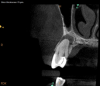

Lastly, regardless of the treatment approach pursued, it is essential to tend to the psychological needs of the patient experiencing a flare-up. The patient should be reassured that the condition is treatable and that flare-ups are quite distinct from treatment failure. In fact, their occurrence has not been shown to affect the overall prognosis of NSRCT (Figure 2 through Figure 5).39,40 Because significant preoperative pain complaints have been associated with a greater risk of flare-up, these patients should be counseled and duly warned of the possible occurrence of a flare-up. Simple discussions on pain management and after-hours emergency availability can significantly reduce the stress of flare-ups for providers and patients alike.14

Fig 3. Case demonstrating successful healing of tooth No. 5 following a flare-up incident. Fig 2: Patient presented with asymptomatic apical periodontitis of tooth No. 5. Fig 3: Following initiation of NSRCT, the patient developed a flare-up with swelling and pain. Amoxicillin was prescribed and the calcium hydroxide medicament was replaced. Fig 4: The patient returned 3 months later with radiographic healing of the apical periodontium. Fig 5: Obturation was completed.

Figure 3